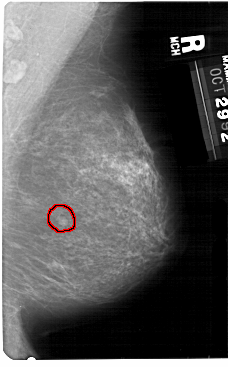

A_1418_1.RIGHT_CC

RIGHT_CC LINES 5491 PIXELS_PER_LINE 2746 BITS_PER_PIXEL 12 RESOLUTION 43.5 OVERLAY

FILE: A_1418_1.RIGHT_CC.OVERLAY

TOTAL_ABNORMALITIES 1

ABNORMALITY 1

LESION_TYPE MASS SHAPE LOBULATED MARGINS CIRCUMSCRIBED

ASSESSMENT 4

SUBTLETY 4

PATHOLOGY BENIGN

TOTAL_OUTLINES 1

BOUNDARY